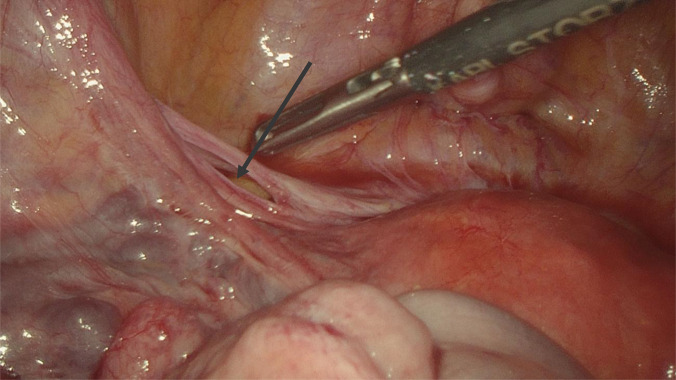

Case description: We treated a 42-year-old female airline cabin crew member who presented with colicky abdominal pain, bilious vomiting, and lower abdominal tenderness. Her abdominal computed tomography (CT) scan showed small bowel obstruction with loops of small bowel predominantly in the left lower abdomen. She had a history of a single episode of similar abdominal pain many years prior, which resolved spontaneously. The rest of her history was unremarkable. She received nonoperative management initially, but due to persistent abdominal pain and vomiting, a diagnostic laparoscopy was done. The diagnostic laparoscopy showed congested but viable small bowel herniating into a peritoneal defect through the lateral part of left broad ligament at the lateral pelvic wall into the retroperitoneum. The hernia was reduced, and the defect was repaired. Postoperatively, she had an uncomplicated recovery.